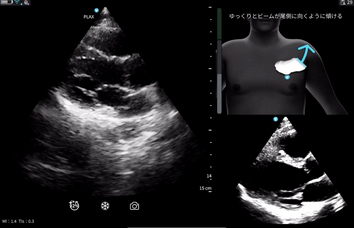

※Cardiac Guidance/ Interpretationの実際の画面

※Cardiac Guidanceによる心エコー検査のリアルタイムガイド表示機能。Quality Meterで画像クオリティを確認,画面上部にはイラストとともに「時計回りにゆっくりと回転」などリアルタイムに様々なガイダンスが表示される。

「Vscan Air SL Ally」には,心エコー検査をサポートする Cardiac Guidance機能とCardiac Interpretation機能が備わっている。Cardiac Guidanceは,検査手技をAIがリアルタイムでガイドしながら,画像の品質を担保し,一方のCardiac Interpretationは,取得した画像をAIが解析し,診断精度を引き上げる。

リアルタイムで操作者をサポートするガイド機能で,プローブ(探触子)の位置,角度,肋間操作,深度を画面上で指示し,より正確で高品質な画像取得をサポートする。さらに,画像品質のインジケータ機能を備えており,最適なスキャン画像が得られているか否かを判定する。また,一定レベル以上の品質を認識した際には,プローブを一定時間保持することで自動的に画像を保存する。Cardiac Guidanceの機能により,複雑な心エコー検査を簡便かつ正確に実施することが可能となり,臨床現場だけでなく,大学や基幹病院のトレーニングセンターでの教育利用にも「Vscan Air SL Ally」の導入が期待される。